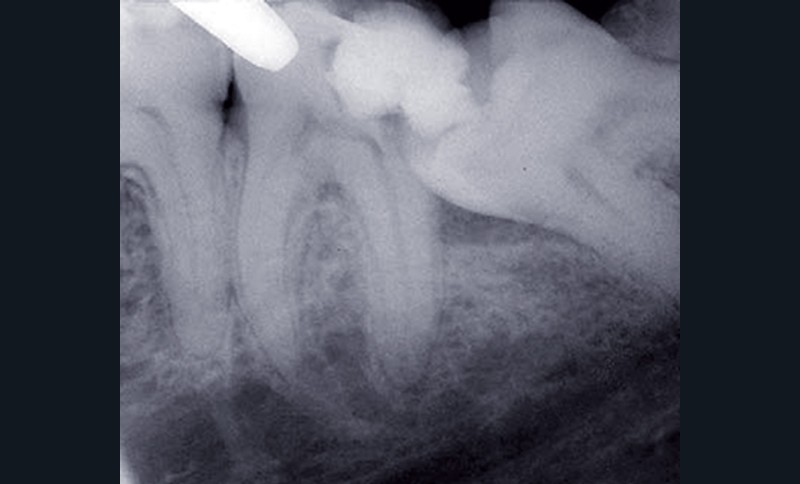

Lésion carieuse de la dent de sagesse et/ou de la deuxième molaire adjacente

Ces lésions sont d’autant plus probables que la dent de sagesse est en situation mésioversée et bloquée par la 2e molaire (fig. 3). L’appui continu de la couronne de la 3e molaire sur la face distale de la 2e peut provoquer des lésions carieuses du collet ou de la couronne, une rhizalyse ou conduire à la mortification.